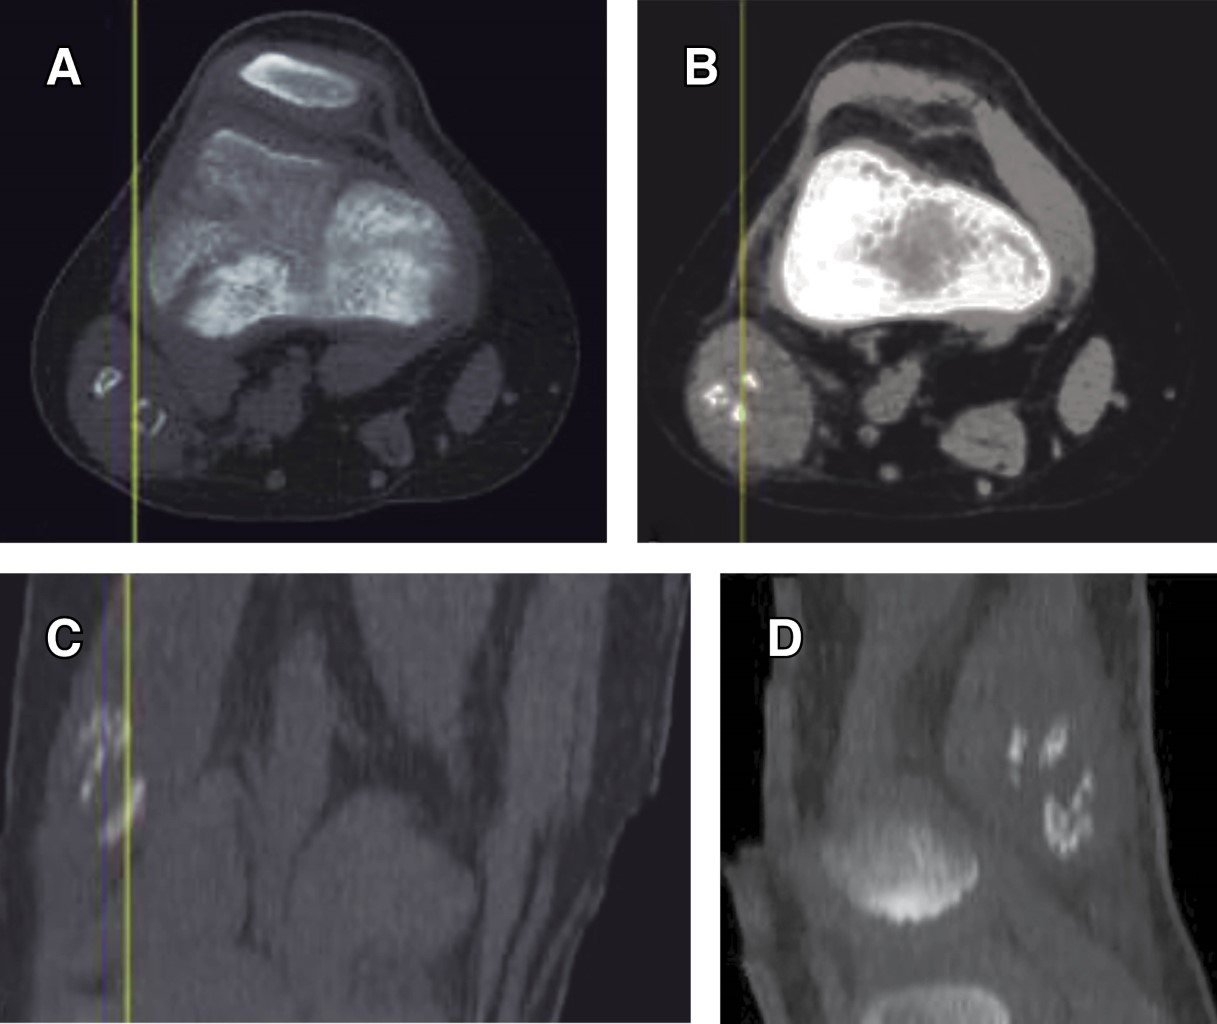

Introduction: myositis ossificans (MO) is described as a non-neoplasic heterotopic bone formation at soft tissues and muscle. It is a rare entity in children, but it must be included within the differential diagnosis of a malignant tumor or an infection. Material and methods: the objective of this retrospective study is to describe three clinical cases of circumscribed myositis ossificans; the first one is a 10-year-old girl with a post-traumatic cervical injury, the second one is an 11-year-old boy with an atraumatic-type distal thigh injury, and the third one is an 8-year-old boy with a post-traumatic right thigh tumor. Results: the diagnosis was made on the basis of the clinical presentation, radiologic imaging and histopathological findings. The results obtained by conservative treatment were good in all cases, with resolution of pain and progressive reduction in size of lesions, without registering complications during follow-up. Conclusion: myositis ossificans is a rare entity, whose diagnosis is usually complex and may require a multidisciplinary team, and whose prognosis is nevertheless favorable.

Figure 1

Figure 2

Figure 3

Figure 4